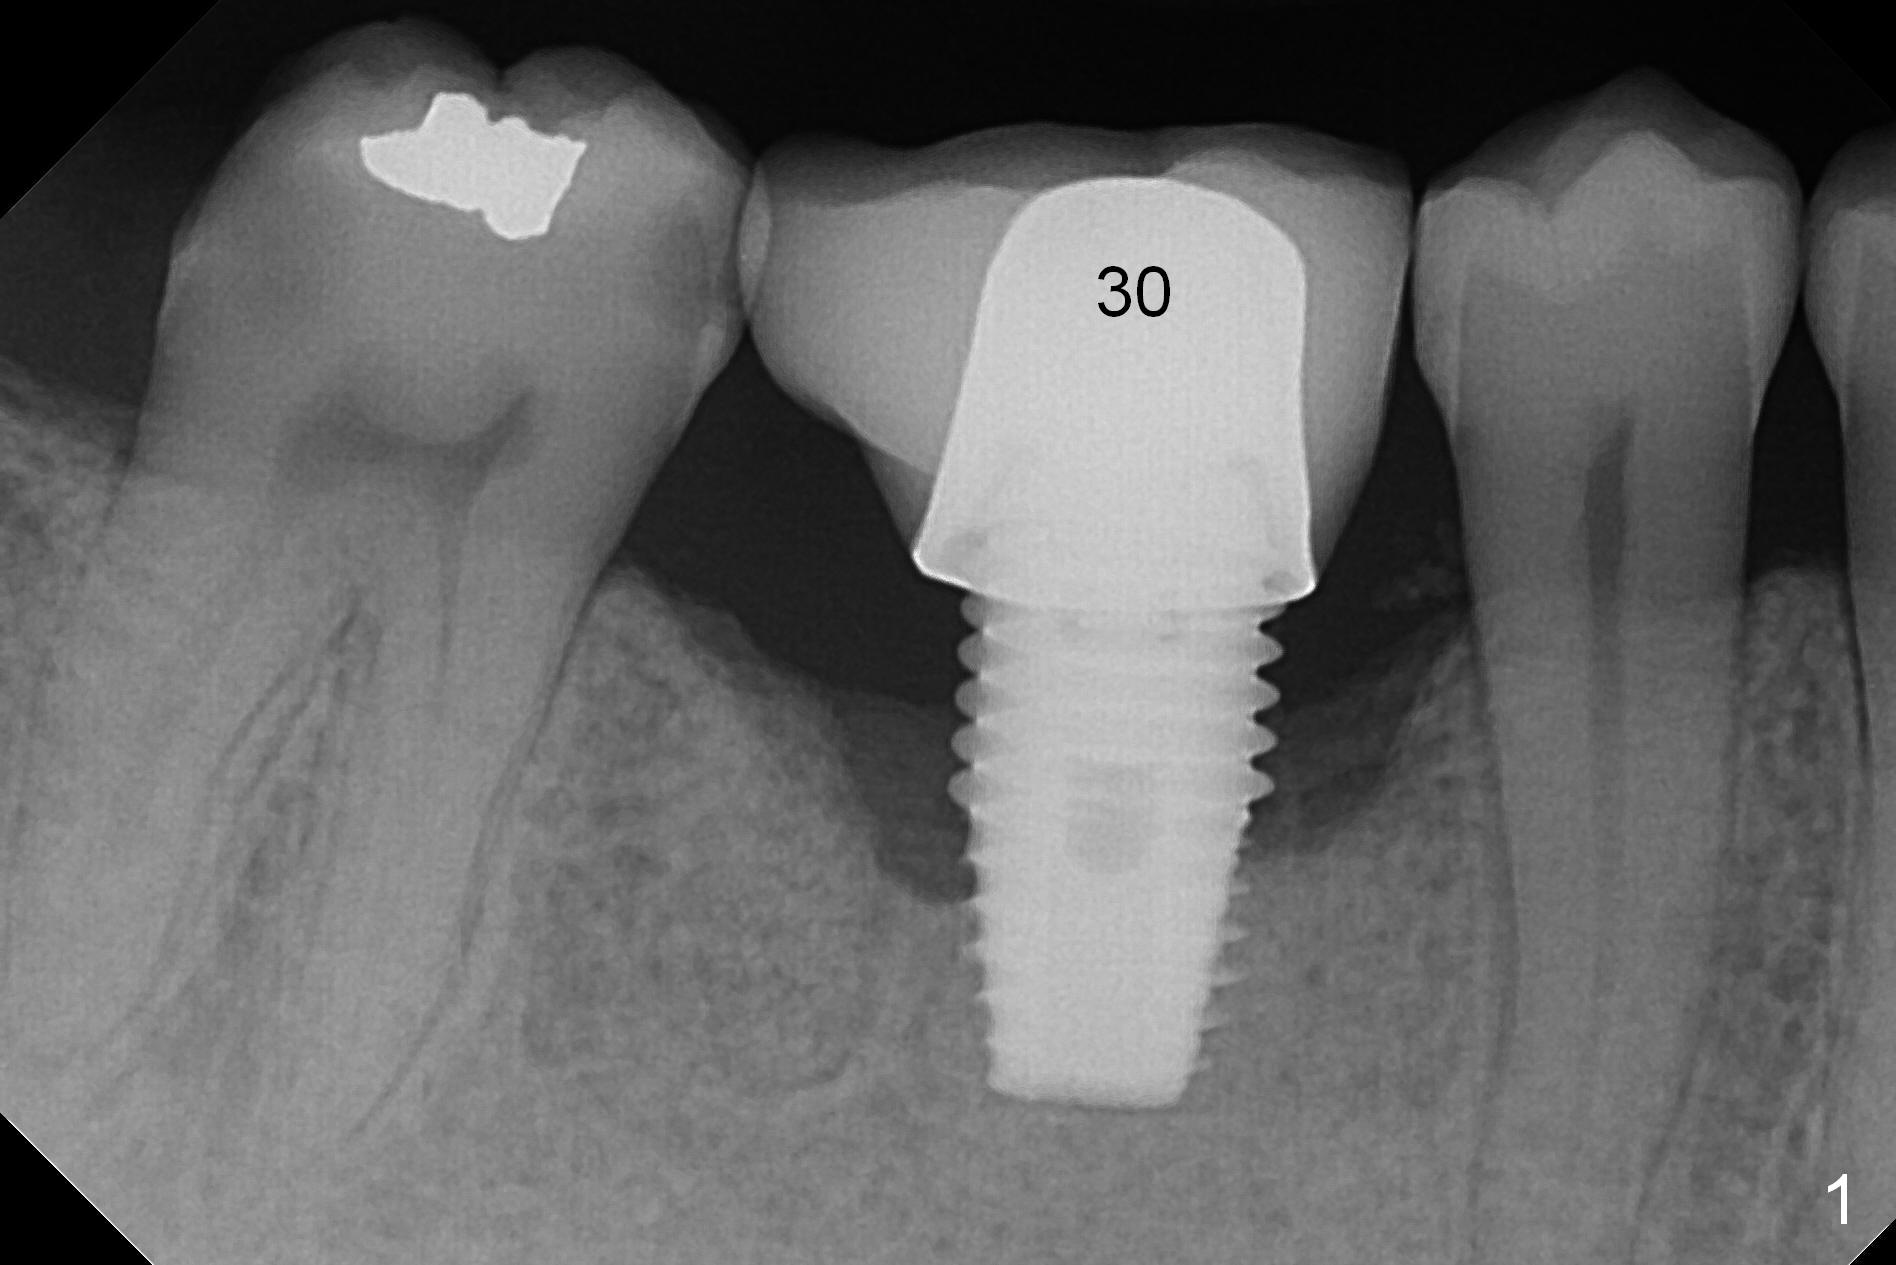

A 49-year-old man develops acute abscess of the lower right quadrant (Fig.3-5) secondary to periimplantitis at #30 (Fig.1,2,6). The latter is probably due to buccal placement (Fig.6 (*: buccal plate)). After removal of the infected implant, an osteotomy is established as lingual as possible using single drill modality (Fig.7 (4.3 mm Magic Drill after 1.6 mm pilot drill and Marking Bur, then Final Drill). With the single drill, the osteotomy does not shift buccally in spite of the lower buccal plate. A 5x9 mm IBS implant is placed lingually as planned (Fig.8 (>40 Ncm)), followed by an angled abutment (5 mm x 15° (4 mm)) (Fig.9 A). The buccal gap is filled with autogenous bone, allograft (.5-1.5 mm) and Osteogen (Fig.10 *), covered by resorbable and non-resorbable membranes. After suturing, periodontal dressing is applied.